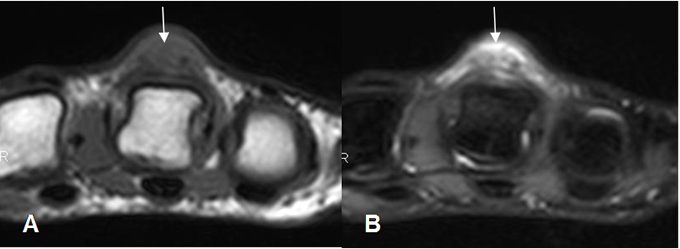

Fig 7. Laceración.

A: RM axial en T1 y B: RM axial en STIR. Igual paciente anterior. Cambios inflamatorios, con ausencia del tendón extensor, por ruptura completa.